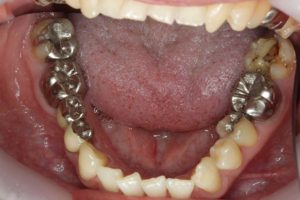

銀歯が多かったのですべて昔の銀歯の下もちりょうしながらセラミックにかえることができてとても満足しています。やっぱり白い歯よいですね。

治療お疲れ様でした。たくさん銀歯が入っていたのですが、最後には真っ白になりましたね。銀歯をやり直す材料にはセラミックとプラスティックがあるのですが、基本的にできるだけプラスティックで治すようにしています。この患者さんも、可能な限りプラスティックで治し、どうしても無理なところだけセラミックにしました。そのため歯を削る量が少ないことに加え、費用もかなり抑えることができます。たくさん治しましたが、全部セラミックで治さなければならないとなっていたら、もっともっと時間も費用もかかっていたかもしれません。当院では、初診時に治療方針や期間や費用などを1時間ほどかけて詳しく説明していますので、患者さんには治療内容について十分納得していただいていると考えています。「親身になって治療してくれる」とおっしゃっていただいたことは、そういったところを評価して頂いたのではいかと思っております。